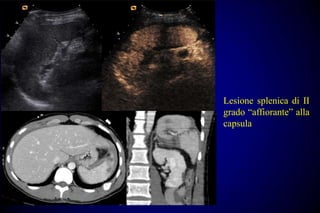

Lesione splenica di II

grado “affiorante” alla

capsula